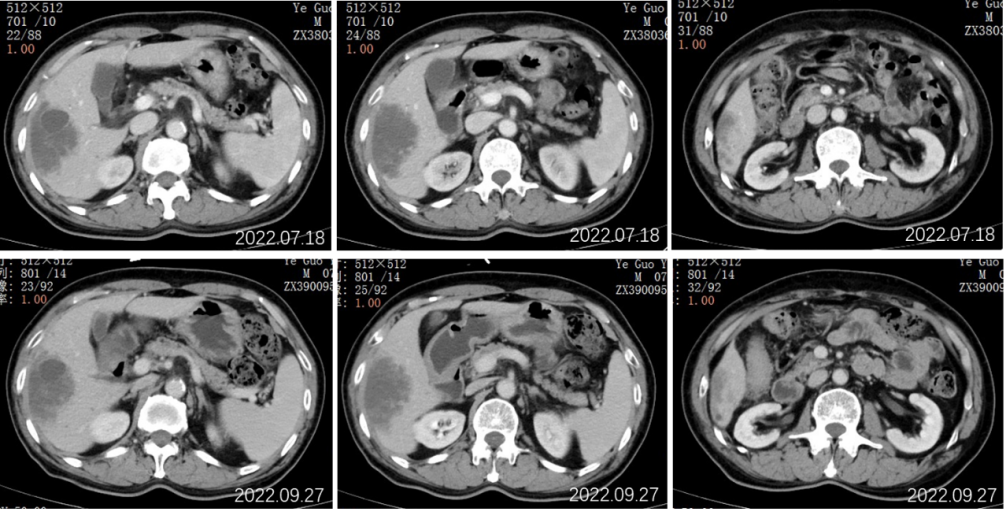

2022.07.19行全腹部平扫+增强:肝右叶可见一类圆形稍低密度影,累及肝S5-8段,边界欠清,约80mm*50mm*98mm大小,密度欠均匀,增强动脉期病灶边缘轻度强化,门脉期边缘环状强化更为明显,中心见无强化坏死区,病灶周围S6段另见数个小结节样类似强化灶;肝内另见数个类圆形低密度灶,径约7-25mm,增强扫描未见强化。

结论:1、肝右叶多发占位,倾向恶性肿瘤,考虑①胆管细胞癌;②转移瘤不除外;2、肝内及双肾多发小囊肿;3、慢性胆囊壁炎改变;4、肝内钙化灶;前列腺钙化灶。

2022.09.27胸部CT平扫:1.两肺多发小结节、类结节影,较前相似,转移性考虑;2.两侧胸腔少量积液较前已吸收。3.左侧第5后肋骨质破坏。

2022.09.27腹部CT增强:肝胆管细胞癌治疗后复查:1、肝右叶多发占位,较前大小相仿,目前仍可见活性;2、肝内及双肾多发小囊肿,相仿;肝S2段小血管瘤考虑,相仿;3、慢性胆囊炎改变;4、肝内钙化灶;前列腺钙化灶。

2022.11.25腹部CT增强:肝胆管细胞癌治疗后复查:对比2022-09-27日:1、肝右叶多发占位,较前大小相仿,目前仍可见活性;2、肝内及双肾多发小囊肿,相仿;肝S2段小血管瘤考虑,相仿;3、慢性胆囊炎改变;4、肝内钙化灶;前列腺钙化灶。

2023.5.28腹部CT增强:肝胆管细胞癌治疗后复查:对比2022-11-25日:1、肝右叶多发占位,较前相仿;2、肝内及双肾多发小囊肿,肝S2小血管瘤,大致相仿;3、慢性胆囊炎改变;胆囊内点状结石未见显示;4、肝内钙化灶;前列腺钙化灶。

2023.09.29腹部增强CT:肝胆管细胞癌治疗后复查:对比2023-05-28日:1、肝右叶多发占位,较前大致相仿;2、肝内及双肾多发小囊肿,肝S2小血管瘤,大致相仿;3、慢性胆囊炎改变;胆囊周围渗出,较前稍增多;4、肝内钙化灶;前列腺钙化灶;新见盆腔少量积液。